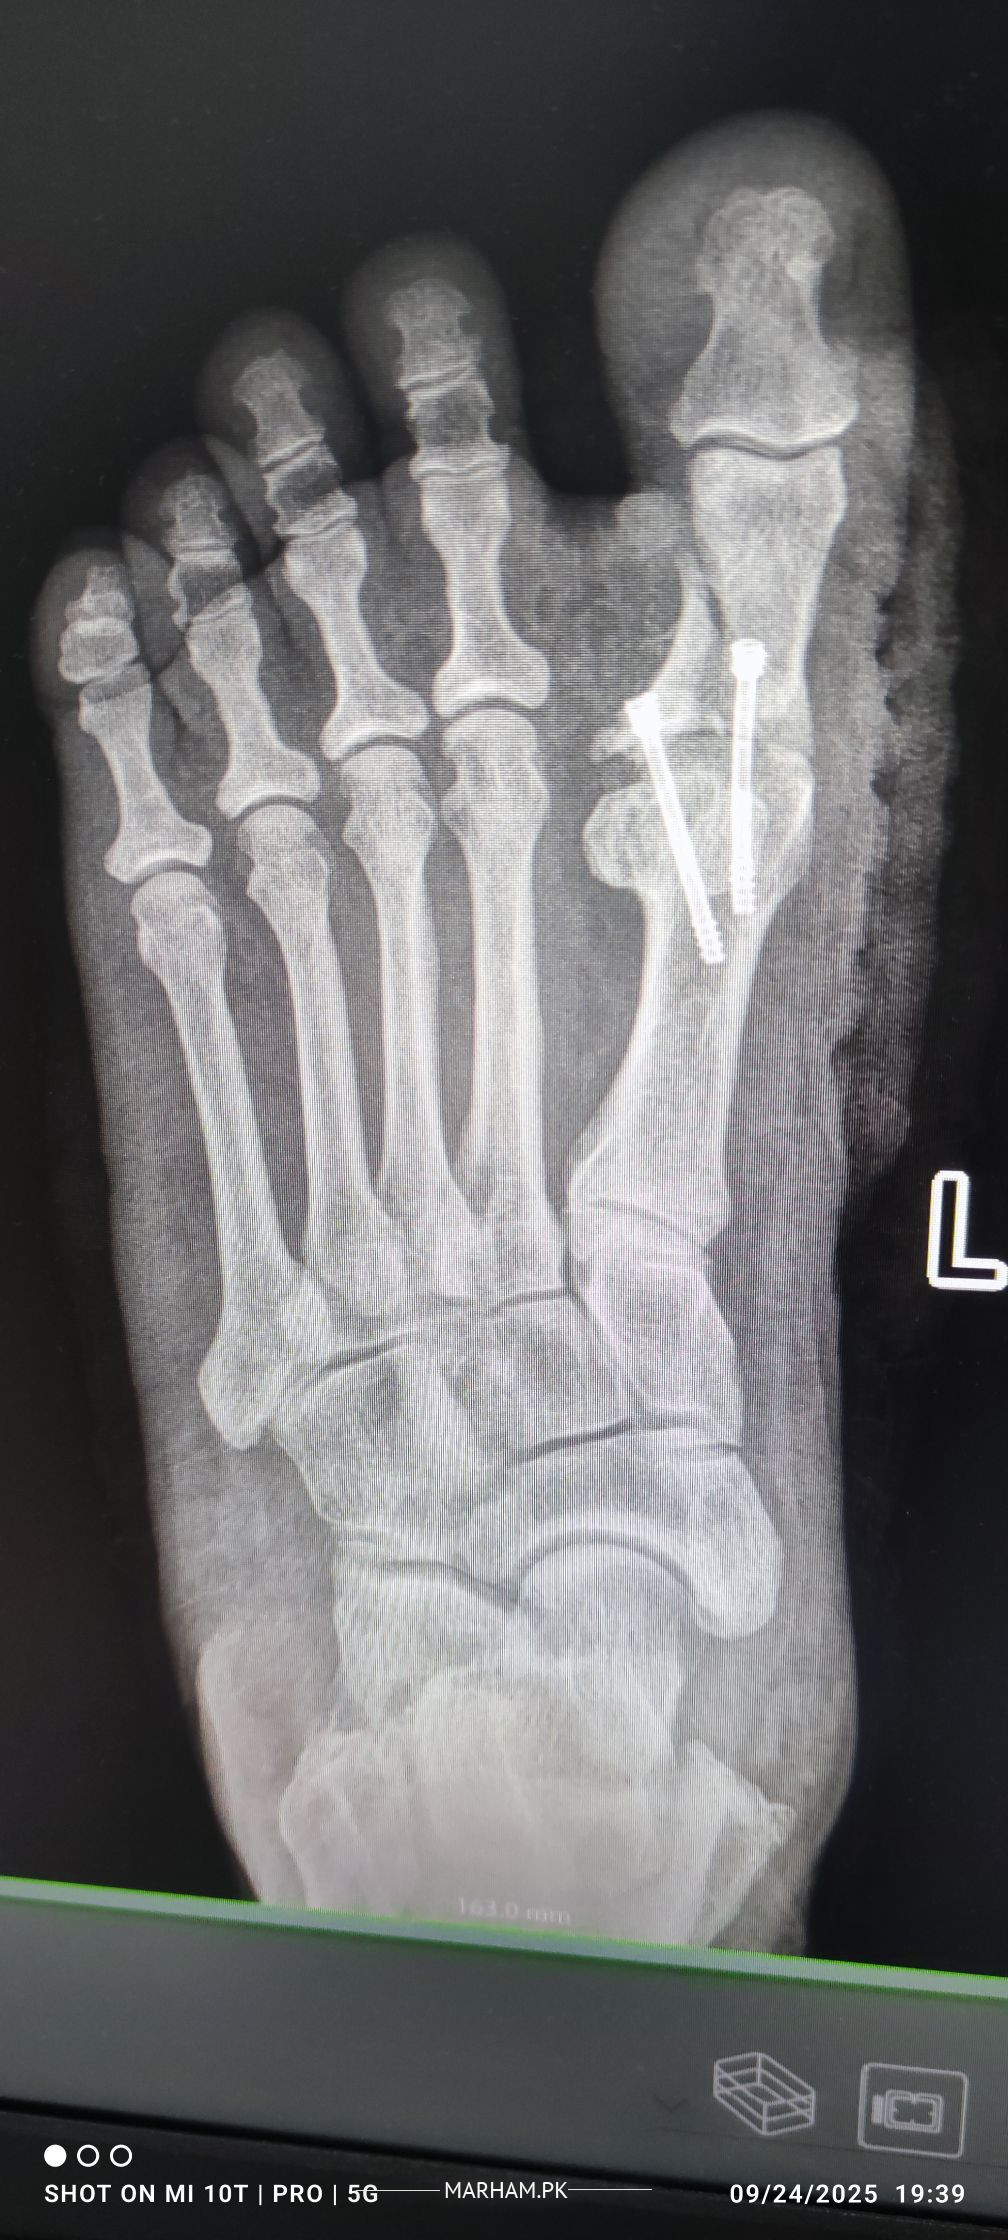

AoA, kindly ye meri mother ki xray report daikh kar bta dain k operation theek ho gya hai, X-ray main fracture nazar aa rha hai lekin, technician ny b kaha k fracture show ho rha hai kisi doctor ko dikha dain. shukria

Need following informations

1- Date of injury or weeks

2- XRay before Surgery

3- XRay just after surgery

4- XRay latest , you already shared

Regards

Osteotomy means cutting the bone to straighten it, usually to relieve pain or improve joint function. After the cut, the bone is held in place with plates, screws or pins while it heals. Most people need a period of limited weight‑bearing followed by physical therapy to rebuild strength and range of motion. Recovery can take several months, and the goal is to return to normal activities, but some patients may still need braces or activity adjustments. The procedure is common for knee, hip or foot problems, and outcomes are generally good when the surgeon’s plan matches the patient’s anatomy and the rehab is followed closely. If you’re considering it, talk to an orthopedic surgeon about your specific condition, the expected healing time, and any lifestyle changes that will help you recover fully.